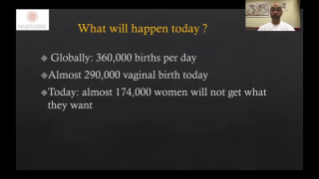

L'optimisation des flux de travail en gynÊcologie et obstÊtrique est indispensable pour traiter les volumes importants de patientes se prÊsentant pour des dÊpistages. Par exemple, les malformations du système nerveux central (SNC) font partie des anomalies congÊnitales les plus frÊquentes. Compte tenu des diffÊrentes conditions dans lesquelles sont rÊalisÊes les Êchographies, par exemple lorsque le f?tus est mal positionnÊ, il est particulièrement difficile de visualiser le plan transcÊrÊbelleux sur les Êchographies 2D. L'automatisation de la dÊtection et de la prise de mesures peut donc grandement amÊliorer l'efficacitÊ de l'imagerie.